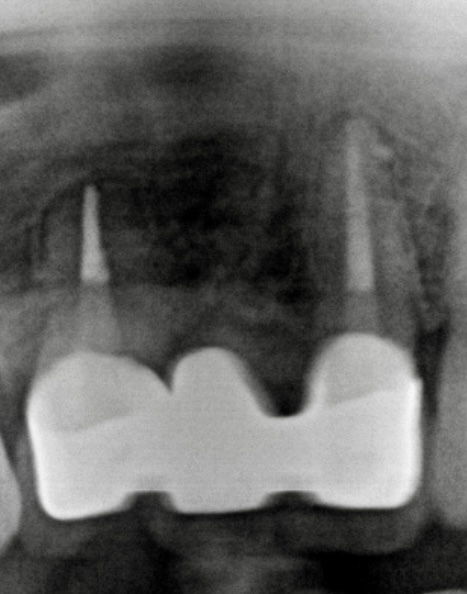

自費根管治療症例2 治療前

左下の奥歯が根の治療を受けているが治らない。

管の分かれている部分に根の治療による穿孔がありました

穿孔部分の封鎖と通常の根管治療を行いました

症状は、完全に消えて、穿孔部分の封鎖と確実な清掃、充填が確認できます

精密根管治療(自費根管治療)治療開始

精密根管治療(自費根管治療)、治療回数3回、治療期間約1ヶ月、治療費(大臼歯再治療)15万3千円+4,500円X3回 ジルコニアクラウン6万9千円

治療後

症状はすべて改善、経過2年後

症状もレントゲン上の炎症も全く再発はありません

向かって奥から2番目審美性も機能も維持されています

治療の特徴

治療は1回1時間程度で複数回。根の壁の封鎖材料は、MTAセメント。副作用もなく穿孔部分位の封鎖には最良な材料です。そのほか、バイオセラミック系の生体活性材料も現在は使用します。マイクロスコープを使用した精密根管治療では、ラバーダムシートの使用、無菌的操作が絶対条件です。